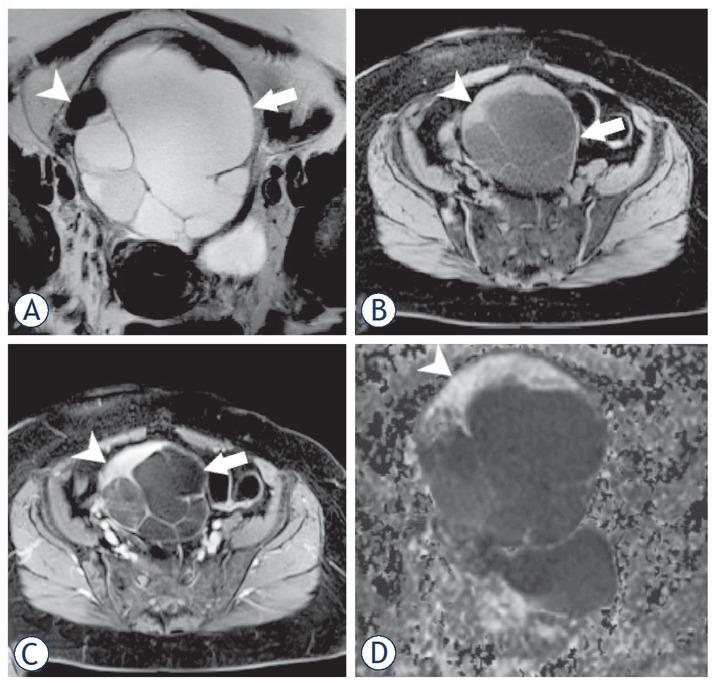

Figure 4